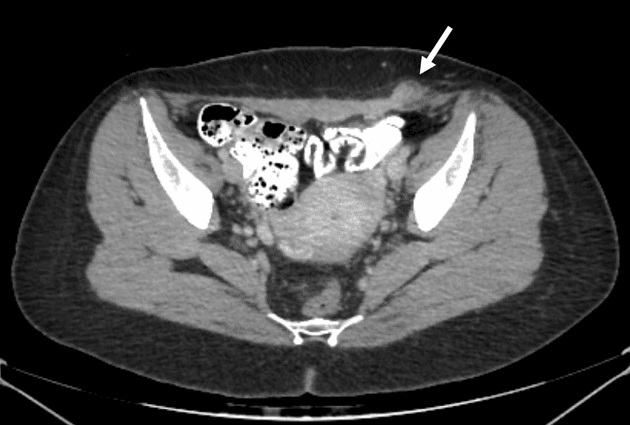

Axial C+ portal venous phase

Có vùng giảm tỷ trọng (hypodense) dưới màng gan, tổ chức mô đệm không đồng nhất tại phân đoạn 3 gan. Vùng này nằm ngay dưới vị trí chèn dụng cụ nội soi tại vùng thượng vị trung tuyến, gợi ý vết rách do chèn dụng cụ. Có hiện tượng phồng màng gan tại chỗ, biểu hiện của một khối máu tụ nhỏ dưới màng gan. Vùng tổn thương có mật độ không đồng nhất, không đặc hiệu trên nghiên cứu một thì, và lan xuống phía các nhánh tĩnh mạch cửa trái. Khuyến cáo thực hiện chụp CT gan nhiều thì (multiphase CT) để loại trừ chảy máu hoạt động và các biến chứng mạch máu do vết rách.

Vết rách gan phân đoạn 3 nằm ngay dưới vị trí chèn dụng cụ nội soi thượng vị, lan dọc theo các nhánh của tĩnh mạch cửa trái (segment 3 hepatic laceration subjacent the epigastric port site and extends down the branches of the left portal vein). Không thấy xuất huyết hoạt động (active hemorrhage) trên nghiên cứu một thì, tuy nhiên do tổn thương gần các mạch máu gan và hình ảnh không đồng nhất, khuyến cáo đánh giá bằng chụp CT gan chuyên biệt nhiều thì để loại trừ biến chứng mạch máu (vascular complication).